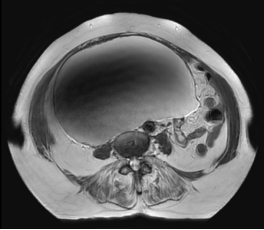

80岁曹奶奶(化名)30年前因子宫肌瘤接受了子宫切除术。半年前出现腹部胀痛,并逐渐加剧,到宁德市医院就诊后发现盆腹腔有一个巨大肿瘤,上界达剑突下。

这个肿瘤在曹奶奶的腹腔内占据了大量空间,甚至压迫到周围脏器,对于一个年过八旬、患有高血压、腰椎压缩性骨折术后等多种疾病的老年患者来说,手术风险呈几何级数增加。

妇科科主任、主任医师陈惠华介绍,单孔腹腔镜手术是一种非常精细的微创技术。手术只需要在肚脐附近开一个3厘米左右的小切口,不需要像传统腹腔镜那样先往肚子里充气。医生会先用特殊缝线在肿瘤表面缝一圈,像扎口袋一样,然后用细针穿刺到肿瘤内部,慢慢把里面的液体抽出来。抽液的同时要不断收紧缝线,还要在胸口压个沙袋帮助排液,等液体抽干净后就把缝线彻底扎紧,防止液体漏出来。最后在腹腔镜的引导下把肿瘤完整切除。

手术台上,如预期所料,曹奶奶的腹腔内因前次手术存在广泛粘连,肠管与肿物粘连,且输尿管紧贴肿物,这给手术分离带来了巨大挑战,主刀医生小心保护周围肠管、输尿管等重要结构,切除肿物,最终通过取物袋将肿瘤装袋完整取出。整台手术历时1个半小时。